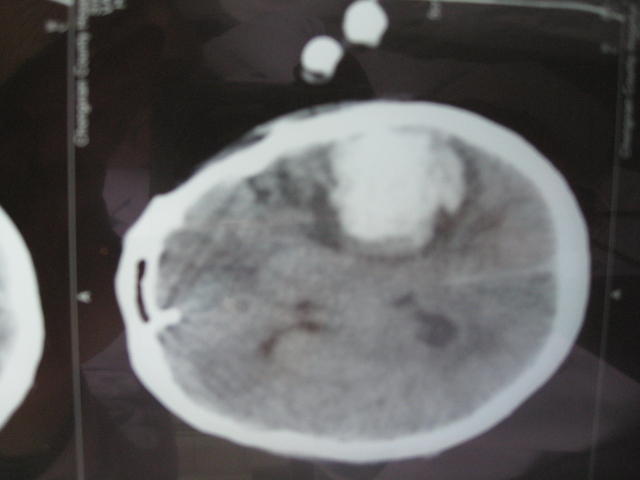

尹** 男 , 56岁,于2008年10月19日11pm以“高血压脑出血”收住院。当时患者昏迷,右侧肢体偏瘫,Bp180/110mmHg,头部CT报告:左侧基底节可见一片状高密度阴影———脑内血肿(量约45ml)。次日8Am行颅内血肿微创清除术,清除血量约30ml,术后继续引流出约10ml淤血。术后第二天患者清醒,第三天患侧肢体恢复自主运动,肌力三级。术后13天能自行站立,术后1月能独立行走。复查CT,颅内淤血完全消失。